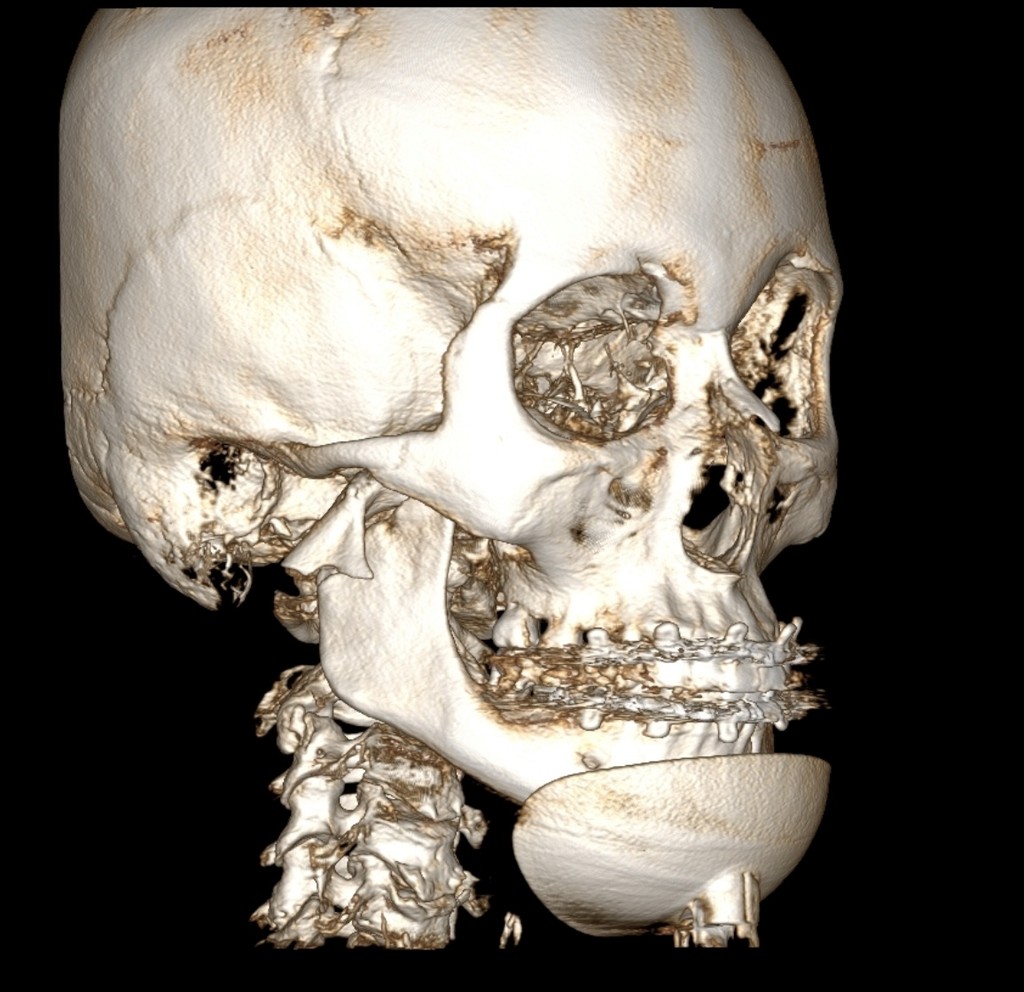

Лінії розлому, зміщення, фрагментацію; етапи зрощення та нормальної консолідації

Ознаки переломів і оцінка консолідації

Роль КПКТ у діагностиці травм

Затримки консолідації, формування хибного суглоба, ураження зубів у зоні перелому